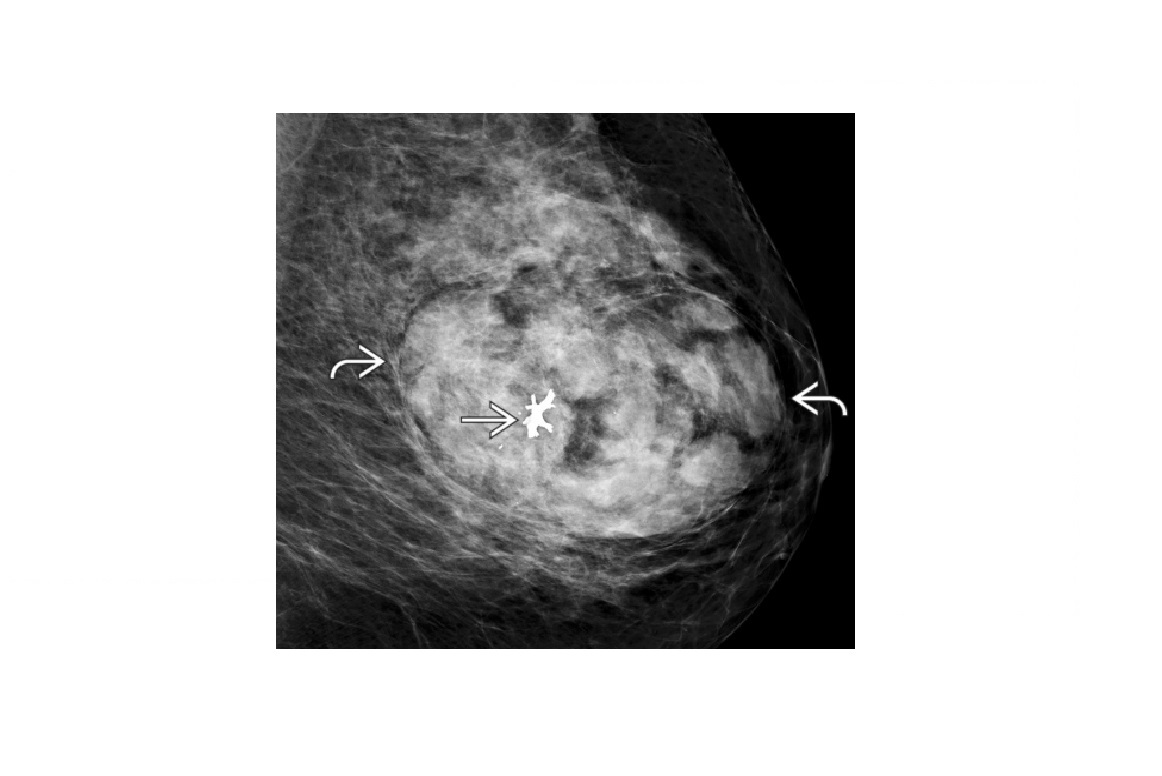

Large well circumscribed, mixed density mass (including Fat and Ca”+), ‘breast within a breast’ apperance?

Hamartoma/fibroadenolipoma